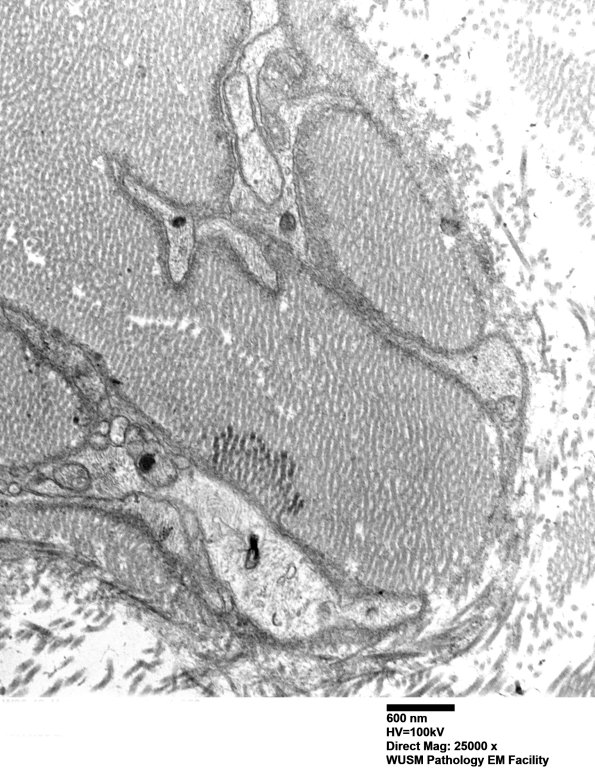

Washington University Experience | PERIPHERAL NEUROPATHY | 4 AXONAL DEGENERATION | 3 Electron Microscopy | 7A6C Chronic Degeneration (Case 33) Sural_056 - Copy

In this collection of processes and collagen it appears most processes are Schwannian in origin. (electron micrographs)